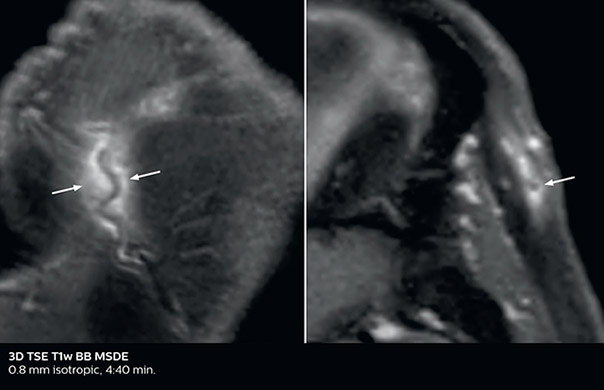

So, what is the actual impact of having more information and more diagnostic confidence? According to Dr. Savatovsky, “One of the indications I’ve seen where using Elition is most impactful is in patients with suspected giant cell arteritis. As an ophthalmologic hospital, we see many patients with suspected giant cell arteritis. Usually we were performing MRI to help us rule out an ischemic stroke, and to verify that the supra aortic vessels are undamaged. With Elition, we still do this, but now we can add on more detailed high-resolution black-blood sequences on superficial arteries. This provides us with high confidence levels for diagnosis of giant cell arteritis (GCA) and as a result, some patients are not sent for a biopsy anymore. A patient who has a normal MRI will not require a biopsy and can be discharged from the hospital in the same day. Before, such a patient would have to stay for about a week, just to find that their biopsy results were negative. We have at least three or four patients a week with suspected giant cell arteritis. For a great deal of these patients we can have a direct impact on their hospital stay.”

The 3D TSE T1w black blood MSDE sequence with fat suppression has an isotropic 0.8 mm voxel size and sagittal oblique and axial reformats are made. The images show superficial temporal artery thickening and peri-arterial fat infiltration. The 3D TSE PDw black blood MSDE with fat suppression has 0.55 mm isotropic voxels. The images shows focal involvement of the frontal branch of the superficial temporal artery.